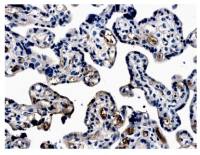

WB analysis of extracts from JK cells (lane 2) using GTX55316 Cyclin H (phospho Thr315) antibody.

Left : Primary antibody pre-incubated with the antigen specific peptide

Right : Primary antibody